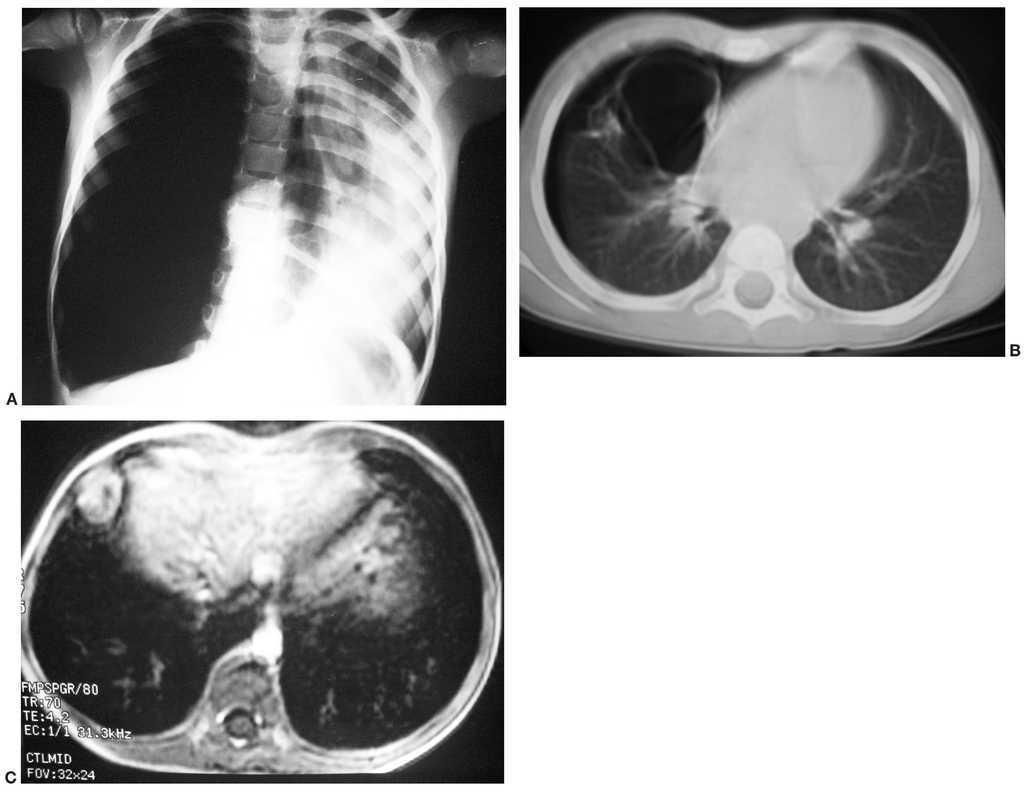

Se trata de una niña de 3 años y 10 meses, a la que se le practicó una radiografía de tórax en la que se halló de forma incidental dos masas pulmonares sólidas, una en el lóbulo superior derecho y otra en la língula (fig. 1). La TC confirmó la presencia de las dos masas, de localización pulmonar, homogéneas y de bordes bien definidos. No presentaba otros hallazgos radiológicos ni enfermedad metastásica. Se realizó una biopsia pulmonar que mostró una tumoración con células pequeñas, redondas y azules en un estroma mixoide. Las células expresan vimentina y focalmente desmina, siendo compatible con BPP tipo III. Tras tres ciclos de quimioterapia se intervino. Actualmente se encuentra estable y libre de enfermedad tras 14 años.

Fig. 1. Caso 1. (A) Radiografía anteroposterior de tórax. (B) y (C) Tomografía computarizada de tórax, cortes axiales con ventana pulmonar. Masas pulmonares sólidas, bilaterales, bien delimitadas, una en el vértice superior derecho

y otra de mayor tamaño en la língula; ambas se mostraban hipocaptantes y homogéneas (no mostrado). Ausencia de infiltración de la pared torácica.